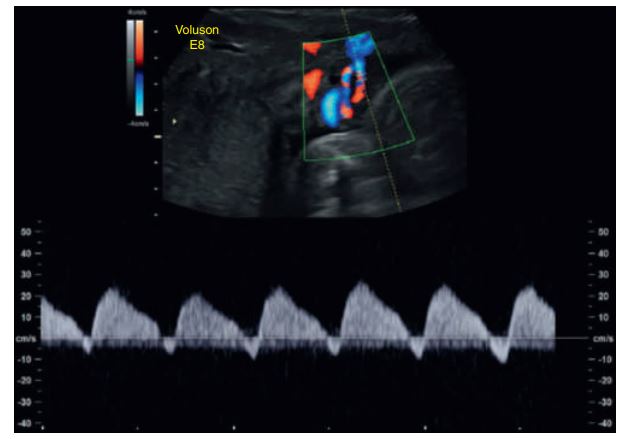

During the fetal cardiac cycle, there is umbilical blood flow during both the pumping (systole) and filling (diastole) phases of the heartbeat.

No flow (absent end-diastolic flow) and_______ during diastole .

signs of fetal jeopardy and may prompt the obstetrician to do further fetal well-being testing or even to deliver the fetuses.

Reversal of diastolic flow in a twin gestation with twin-totwin transfusion syndrome.